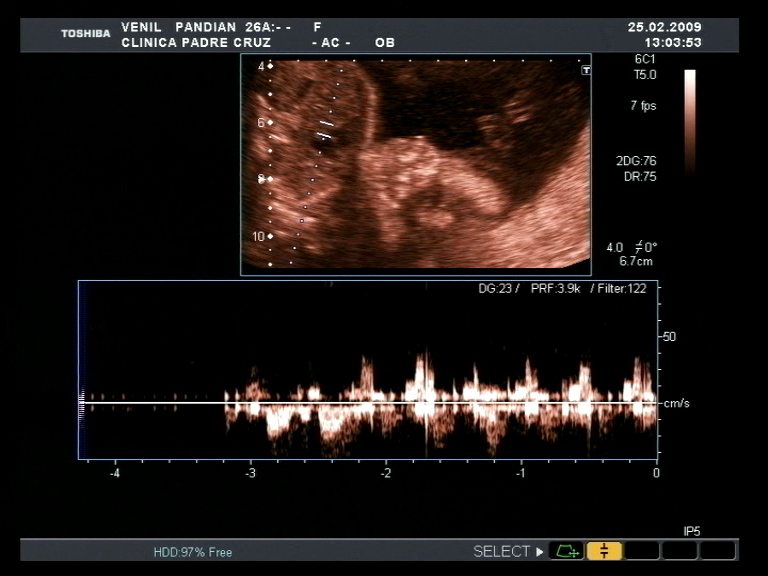

என் மகள், எல்லாத் தந்தையையும் போல் என்னையும் ஒரு "ஆனந்தத் திமிருடன்" நடக்கச் செய்தவள்; பிறந்தது முதல் மட்டுமல்ல; என்னவளின் கருப்பையில் கருவுற்றது முதலே. மேலே காணப்படும் புகைப்படங்கள் அவள் கருவாய் என் மனைவி (என்னவள்) "வேனில்"-இன் கருவறையில் இருந்த போது எடுக்கப்பட்டவை. எனக்கு இன்னும் நினைவில் இருக்கிறது அந்த நாள், 2009 ஆம் ஆண்டு, "பிப்ரவரி" மாதம் 25 ஆம் நாள். எங்களுக்கு பிறக்கப் போகும் உயிர் ஒரு "பெண்" என உணர்ந்த நாள். என்னவள் இன்னுமொரு "தாயை" இந்த உலகுக்கு ஈயப் போகிறாள் என்று உணர்ந்த நாள். இந்திய நேரப் படி சுமார் 17:40 மணி இருக்கும் - நாங்கள் அதை உணர்ந்த நேரம். அந்த கருவின் உறுப்புகள் சரியாக இருக்கிறதா என சரிபார்க்க மருத்துவர் "எம்மகளின்" கால்களை ஒரு மருத்துவக் கருவி கொண்டு, மெதுவாய்(தான்!!!) தட்டுகிறார், உணர்ச்சிப் பெறச்செய்து அவைகளின் செயல்பாட்டை சரிபார்க்க! அவள் கால்களை அசைத்த இன்ப-வலி தந்த அனுபவத்தில் என்னவள் மகிழ்ச்சியுடன் சிணுங்குகிறாள்!! நானோ மருத்துவர் எங்கள் மகளின் கால்களை அடிக்கிறாரே என்ற உணர்ச்சி கலந்த மிரட்ச்சியில் கண் கலங்குகிறேன் (அது ஒரு சோதனை என்பது தெளிவாய் தெரிந்திருந்தும்). நம்புங்கள்!!! இதை மீண்டும் நினைவு படுத்தி எழுதும் போது என் கண்கள் இப்போதும் கலங்குகின்றன. வழிந்து வரும் கண்ணீரைத் துடைத்தபடி தான் இதை "தட்டச்சு" செய்கிறேன்.

மனித-இனம் மிக அதிசயமான உணர்ச்சிகளை தன்னுள் கொண்டிருக்கும் உயிரினம். அதிலும் நான் எளிதில் உணர்ச்சி வயப்படக் கூடியவன் என்பதால், இப்போதும் அந்த நிகழ்வு என்னை கண்கலங்கச் செய்துவிட்டது! இது என்னுடையை மகிழ்ச்சியின் அடையாளமாய், அதன் வெளிப்பாடாய் கூட இருக்கலாம். அது தான் எம்மகளின் "இருதயம்" துடிக்கும் ஓசையை தெளிவாய் கேட்ட தினமும்!! ஓரிரு நிமிடத் துளிகள் என் இருதயத்துடிப்பு நின்றுவிட்டதாய் உணர்ந்த தருணம். என்னவள், ஒரு தாய் என்பதால் அவள் மிகவும் கொடுத்து வைத்தவள்! ஏனெனில் இதை அவள் உடல்-ரீதியாகவும் உணர்ந்தாள்; எனக்கு கிடைத்தது இதை உணர்வு பூர்வமாய் உணர மட்டும் தான். இது இயற்கை தானெனும், சில சமயங்களில் இதன் பால் என்னவள் மீது பொறாமைப்பட்டது கூட உண்டு. பரிசோதனை முடிந்து, பரிசோதனைக் கூடத்தை விட்டு வெளியில் வரும் போது இந்திய நேரப்படி சுமார் 18:00 மணி. வெளியில் வந்தவுடன், நான் எதிர்ப்பார்த்தது போல் ஒரு பெண் குழந்தையை கருவுற்றிருக்கும் என் மனைவியை கட்டியணைத்து நன்றி சொன்னேன் (வார்த்தையற்று தான்!). உடனே, நாங்கள் இருவும் இந்தியாவில் இருந்த/ இருக்கும் எங்களிருவரின் தாய்-தந்தையர்க்கு இம்மகிழ்ச்சியான செய்தியை சொன்னோம்; அவர்களின் சந்தோசமும் எங்களை சேர்ந்து கொள்ள, நாங்கள் இருவரும் "அதி-மகிழ்ச்சி" யாய் இருந்த தருணங்களில் ஒன்று அது.